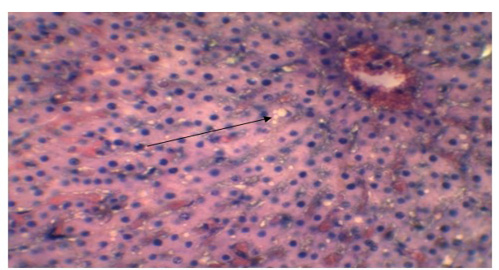

Vacuolar or fatty degeneration in the cytoplasm of hepatocyte (Arrow). (H&E x 40).